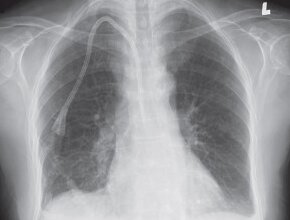

Figure 2. Normal PA chest x-ray for comparison.

A 57-year-old male patient with chest pain. You order a chest x-ray examination (Fig. 1a,b).

Figure 1. a, PA chest x-ray, b, lateral chest x-ray.

Can you identify an abnormality on the PA and on the lateral views?